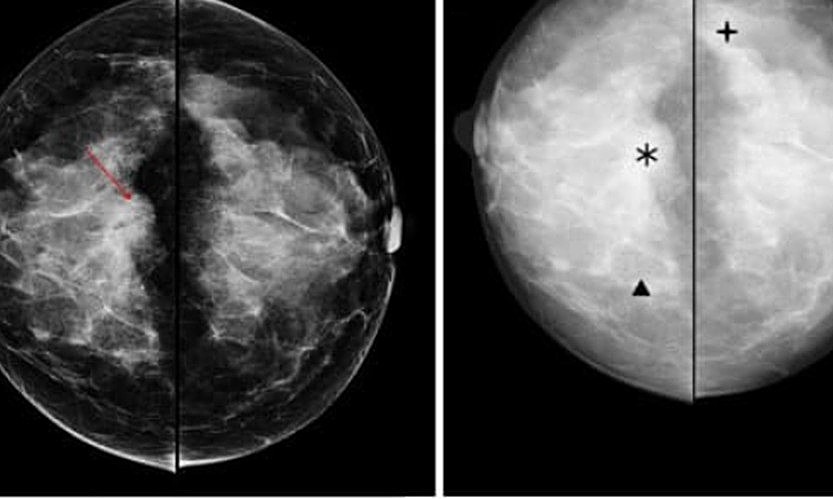

Phân loại BIRADS nhằm mục đích chuẩn hóa việc chẩn đoán, tiên lượng nguy cơ ác tính giúp có thái độ xử trí thích hợp. Kết hợp siêu âm sau chụp X-quang tuyến vú luôn cần thiết trong các tổn thương khó thấy trên nền vú đặc dễ bị bỏ sót.

BI-RADS (Breast Imaging Reporting and Data System) là bảng phân loại được đưa ra bởi hiệp hội điện quang Hoa Kỳ (ACR) nhằm mã hóa các tổn thương trên siêu âm, mammography, MRI vú theo mức độ nguy cơ ung thư. Từ đó giúp cho việc giao tiếp giữa bác sĩ chẩn đoán hình ảnh với bác sĩ khám bệnh và bệnh nhân được đơn giản, dễ dàng giúp cho việc quản lý tổn thương được tốt hơn.

BI-RADS là hệ thống phân loại kết quả chụp Mammography theo điểm số từ 0 đến 5 như sau:

Bảng phân loại BI-RADS gồm có 7 độ, từ 0-6, tương ứng với nguy cơ lành tính và nghi ngờ ác tính của từng tổn thương.